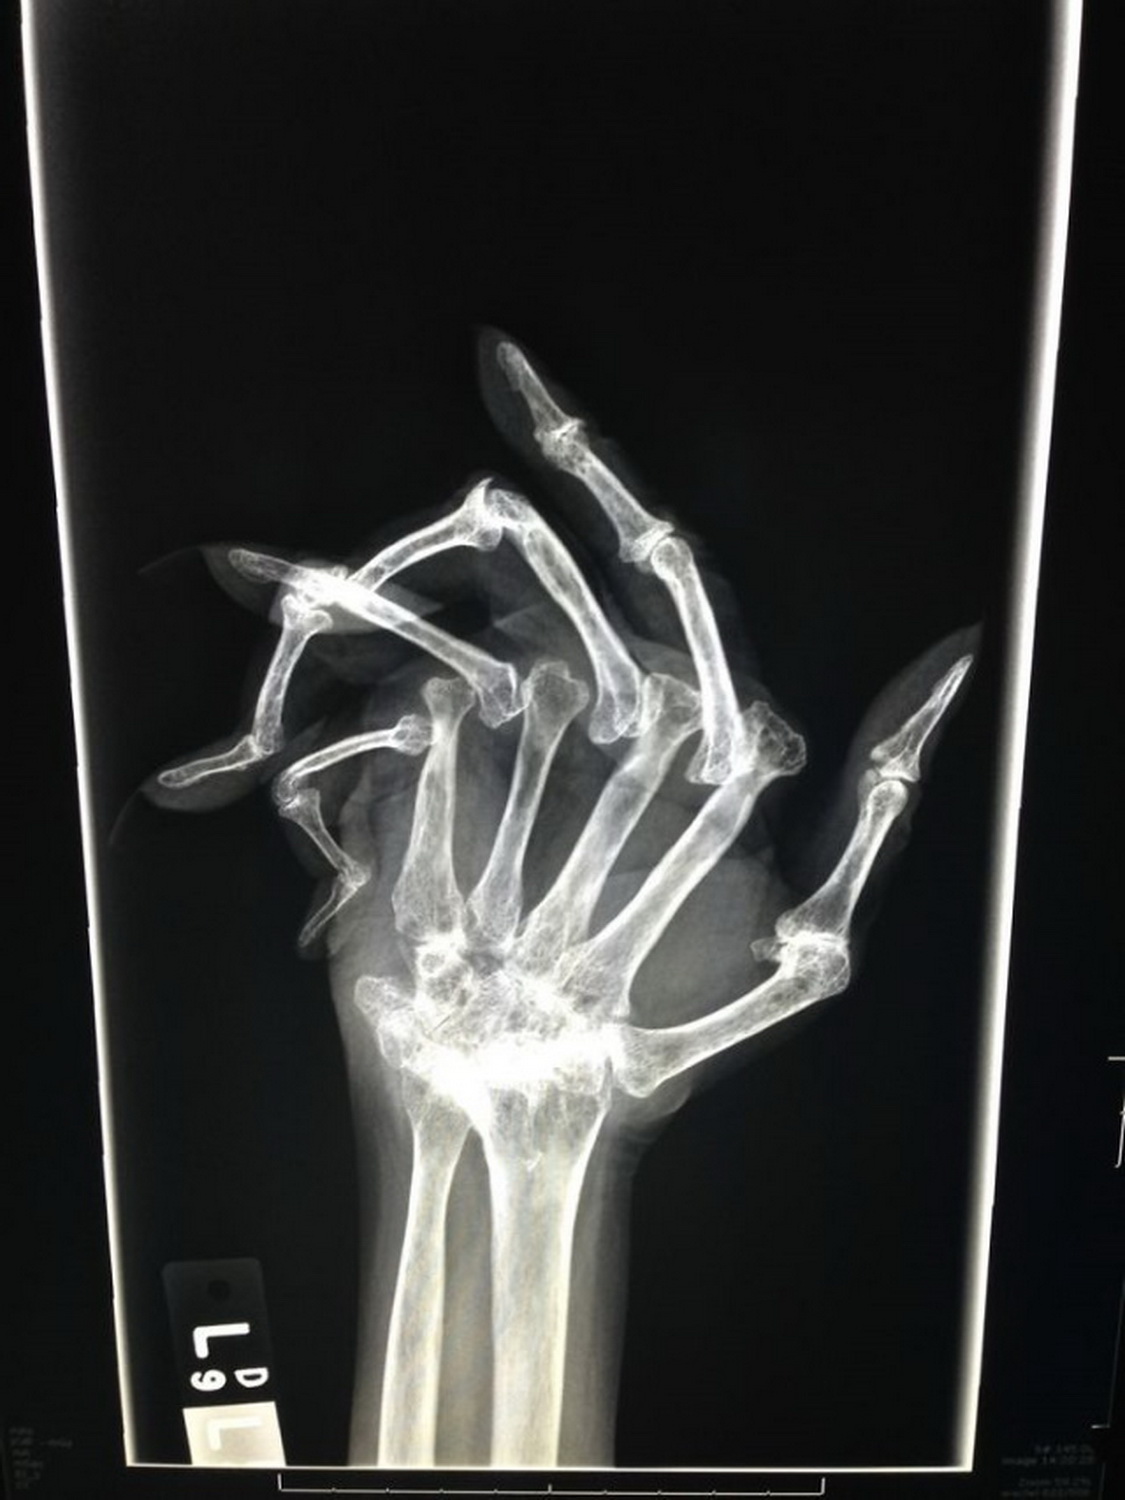

Благодаря регулярно делаемым снимкам видны изменения в костях при ревматоидном артрите в динамике